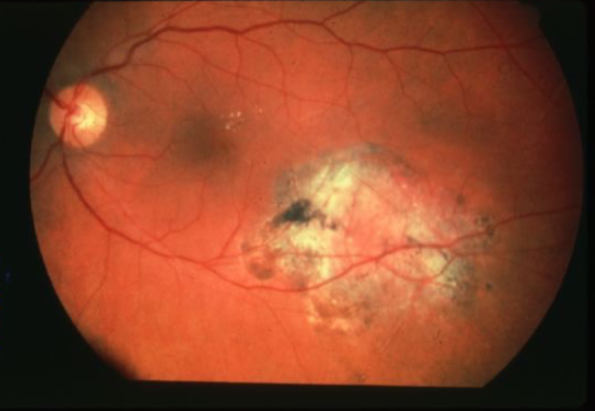

metastatic carcinoma

metastatic carcinoma

metastatic carcinoma

metastatic carcinoma

metastatic carcinoma

metastatic carcinoma

metastatic carcinoma

metastatic carcinoma

metastatic carcinoma

metastatic carcinoma of choroid

more common than primary malignancies

seed of cancer that started in a cancer elsewhere & spread to eye via blood flow

features:

cream, yellow, light brown

flat or slightly elevated mottled pigment clumping on surface

extensive exudative RD

maybe multifocal or bilateral